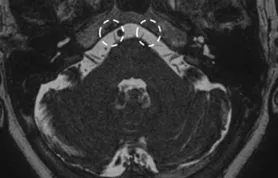

A Steady-state free precession (SSFP) axial image showing the abducens nerves (circles).

A Steady-state free precession (SSFP) axial image showing the glossopharyngeal and vagus nerves (circles).

A Steady-state free precession (SSFP) axial image showing the spinal accessory nerves (circles).

A Steady-state free precession (SSFP) axial image showing the hypoglossal nerves (arrows).